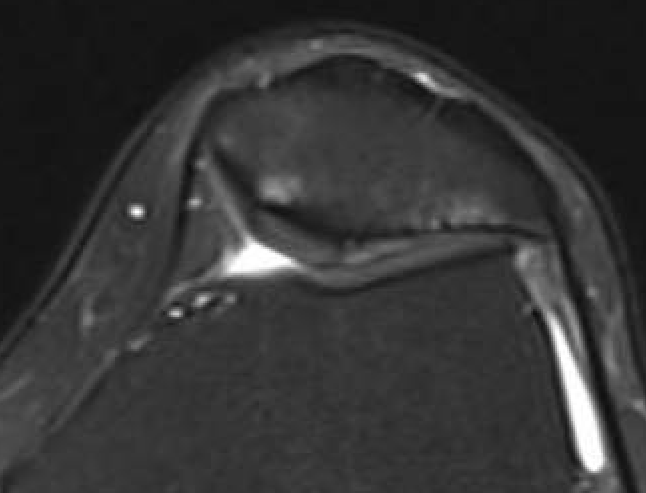

MRI

Moderate lateral facet PJF OA with tilt

Severe lateral PFJ OA in the setting of maltracking / subluxation / tilt